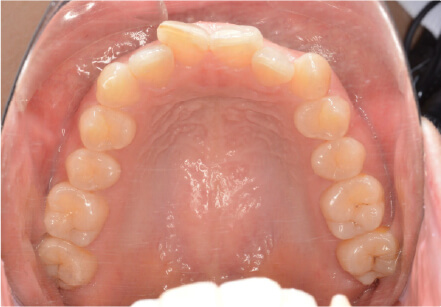

叢生の症例

10歳

女性

相談内容

スペース不足

カウンセリング・診断結果

myoからの移行。スペース不足のためインビザライン開始。

治療内容・方法

全額アライナー矯正

術後の経過・現在の様子

クリアライナー使用

治療のリスク

痛み・歯根吸収・歯肉退縮・虫歯・後戻り

費用・治療期間

(インビザのみ)385,000円、1年2ヶ月 + myo3年4ヶ月